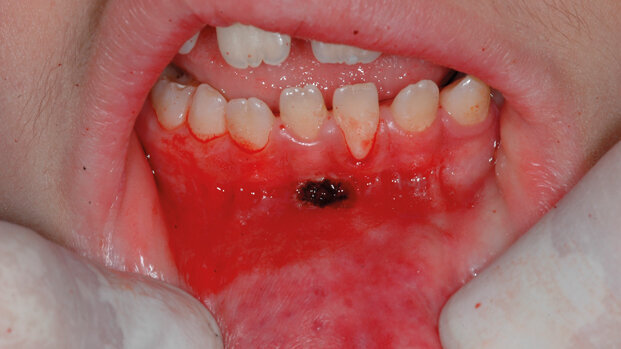

Francesco, 8 anni, pull syndrome

Francesco presentava un frenulo labiale inferiore con inserzione molto alta a livelli della gengiva cheratinizzata tra gli elementi 3.1 e 4.1. Questa inserzione patologica provocava infiammazione e difficoltà nelle normali manovre di igiene orale, con conseguente recessione gengivale a livello del 3.1 (Fig. 9).

Per l’intervento il laser è stato impostato in modalità VLP e parametri di 2,40 W di potenza, 120 mJ con frequenza 20 Hz. È stata usata una punta conica da 12 mm. Al termine del taglio si è utilizzata la fibra 300 micron Nd:YAG per cauterizzare la ferita. Non è stato necessario l’utilizzo di suture e il paziente è stato rimandato a un appuntamento di controllo a 7 giorni (Fig. 10).